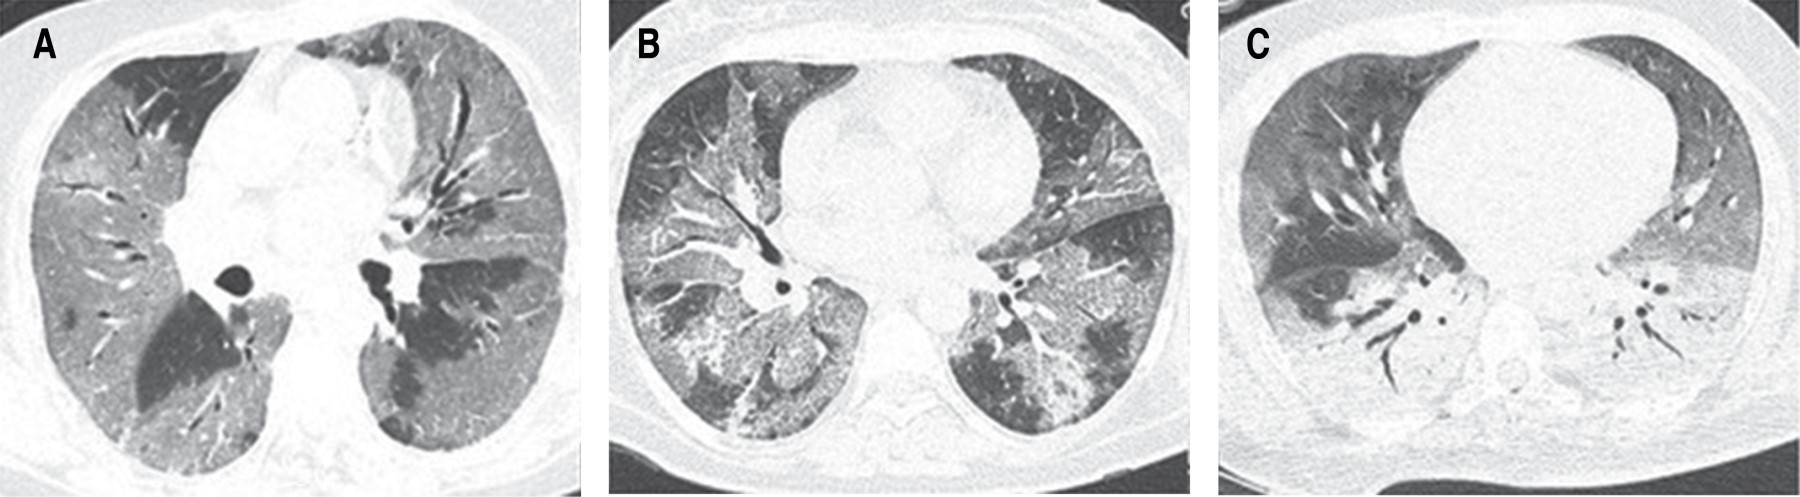

Escala tomográfica para evaluar la gravedad de COVID-19 en el Instituto Nacional de Enfermedades Respiratorias